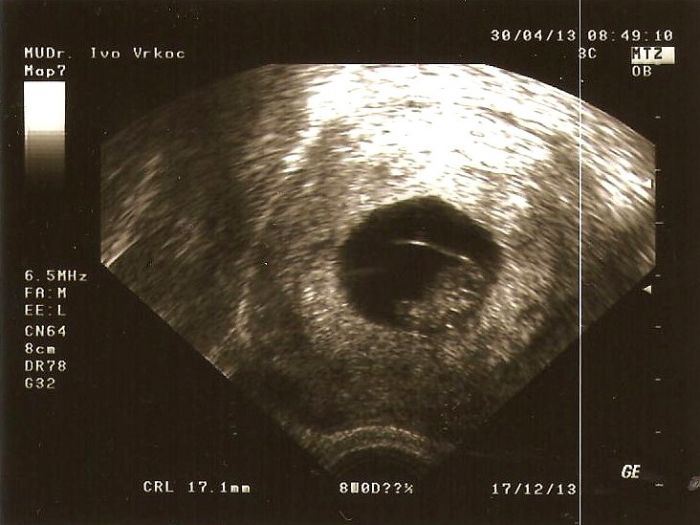

Ahoj holky,tak jsem se dnesk před kontrolou vydala na oční a mám Episkleritis(zánět episkléru a skléru oka) takže jsem dostala nějaké atb kapičky, které kvuli gravitidě dr. vybíral asi 10 min..Bylo mi šíleně a do kontroly ještě pomalu 2 hodiny čas, tak sem cinka s prosíkem sestřičce jestli nemá volné místečko dřív, že nezvládnu nikde 2 hodiny trčet nebo jet mhd domů a pak zase zpět až bude čas, naštěstí je zlatíčko tak říkala že můžu přijít hned.. Čekala jsem chviku a uvnitř se sestřička zděsila že jsem úplně zelená ať si sednu k oknu a měřila mi tlak 90/60 a divila se že jsem zvladla přijít pěšky sama..DR.byl zlatíčko, na vše se mě vyptal a než jsem se nadála už jsem ležela na lehátku a sledovala obrazovku. Původně chtěl dělat utz přes bříško, ale nakonec udělal vnitřní, protože si uvědomil že jsme menší kvuli pozdější ovulce a pak už jsem to moje milovaný zlatíčko uviděla, bylo to úžasný i když to byl zatim jen fliček typu veliká hlavička + zbytek, takže fazolka Pak najel co nejblíž, nechal utz v klidu a ptá se mě:Vidíte jak tam bliká srdíčko? a já nadšeně kývala a usmívala se jak praštěná něčím po hlavě

Odpovídáme 8+2tt tudíž o týden menší než jsme podle ms, CRL je 17,1mm(nechápu jak pozná kostrč na tom flíčku ) Napsal mi ještě 2 balení utroše a říkal že kdybych shodila další 3kg a zvracení neustupovalo že mě nechá ambulantně vypsat na nějakou výživnou kapačku do nemocnice. Další kontrola je 28.5 a příští úterý mě čeká genetika..

Původně mě chtěl dr. odeslat do Gennetu, ale protože tam nejsem ještě ani zavedená, tak mě poslal do nemocnice na genetiku..Jsem strašně šťastná a nemůžu se na tu fotku vynadívat, doufám že tentokrát bude vše v pořádku… ![]()